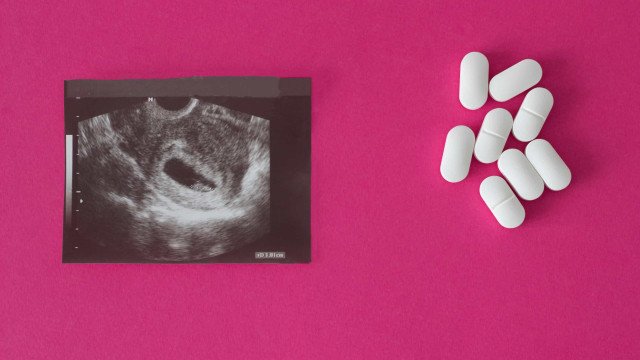

Estado com maior fecundidade de meninas de 10 a 14 anos, Roraima dificulta abortos legais

Casos como o de Amanda são mais comuns do que os de Luísa. Ambas moram no estado com a maior taxa de fecundidade no Brasil para meninas de 10 a 14 anos, conforme levantamento feito pela Folha com base no Censo e no Sinasc (Sistema de Informações sobre Nascidos do Ministério da Saúde), com números de 2022, os últimos consolidados. Os dados do Sinasc podem, ainda, conter algum percentual de subnotificações.

No Brasil, o ato sexual antes dos 14 anos é considerado estupro de vulnerável e a gravidez é considerada de risco para a vida da gestante.

Apenas 25 meninas entre 10 e 13 anos fizeram o aborto legal entre os anos de 2019 e 2023 em Roraima. Enquanto isso, houve 300 nascidos vivos de mães nessa faixa etária no período, de acordo com informações da Secretaria de Saúde do Estado.

Hoje, a legislação permite que o aborto seja feito em três situações: gestação decorrente de estupro, risco à vida da mulher e anencefalia fetal, sem limite da idade gestacional.

O Projeto Antiaborto por Estupro, de autoria do deputado Sóstenes Cavalcante (PL-RJ), quer colocar um teto de 22 semanas na realização de qualquer procedimento de aborto em casos de estupro.

Neste ano, no entanto, há mais um empecilho para quem mora no estado e quer ter acesso ao serviço. A única unidade neonatal de Roraima –que está habilitada a fazer o aborto legal– é a Nossa Senhora de Nazareth. No local, a Folha foi informada pela administração que o procedimento não tem sido feito desde a resolução do CFM (Conselho Federal de Medicina), nº 2.378/2024, que veta a assistolia fetal, procedimento que consiste na injeção de produtos químicos no feto para evitar que ele nasça com sinais vitais.

A técnica é recomendada pela OMS (Organização Mundial de Saúde) e é tida como a melhor prática assistencial à mulher em casos de aborto legal acima de 20 semanas.